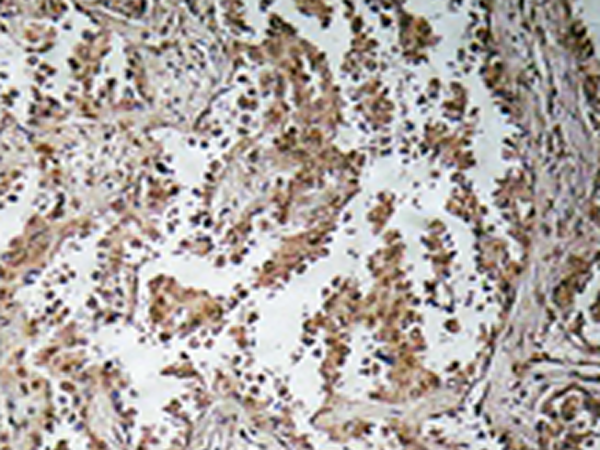

IHC positive control: |

Human lung carcinoma tissue |

IHC Recommend dilution: |

50-100 |